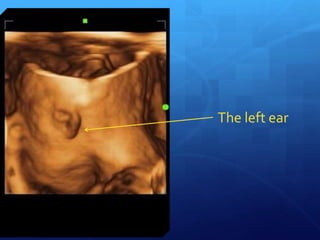

The left ear